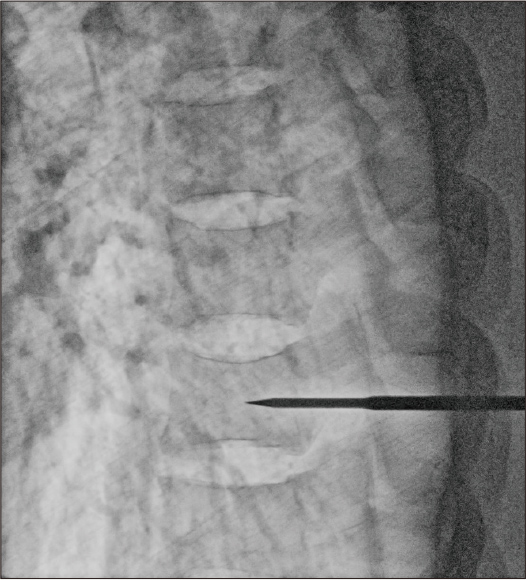

Dynamic processing and noise reduction is performed frame by frame. These conditions enable clear images with less image lag.

Differing thicknesses in areas of the body and nearby structures are recognized from converted 3D information, and the contrast and density are adjusted.

Unstructured noise components are extracted and reduced to improve the granularity of the image. This enables greater visibility of the subject structure.

After applying Dynamic processing

After applying Dynamic processing + noise reduction

Dose: 4.2mA